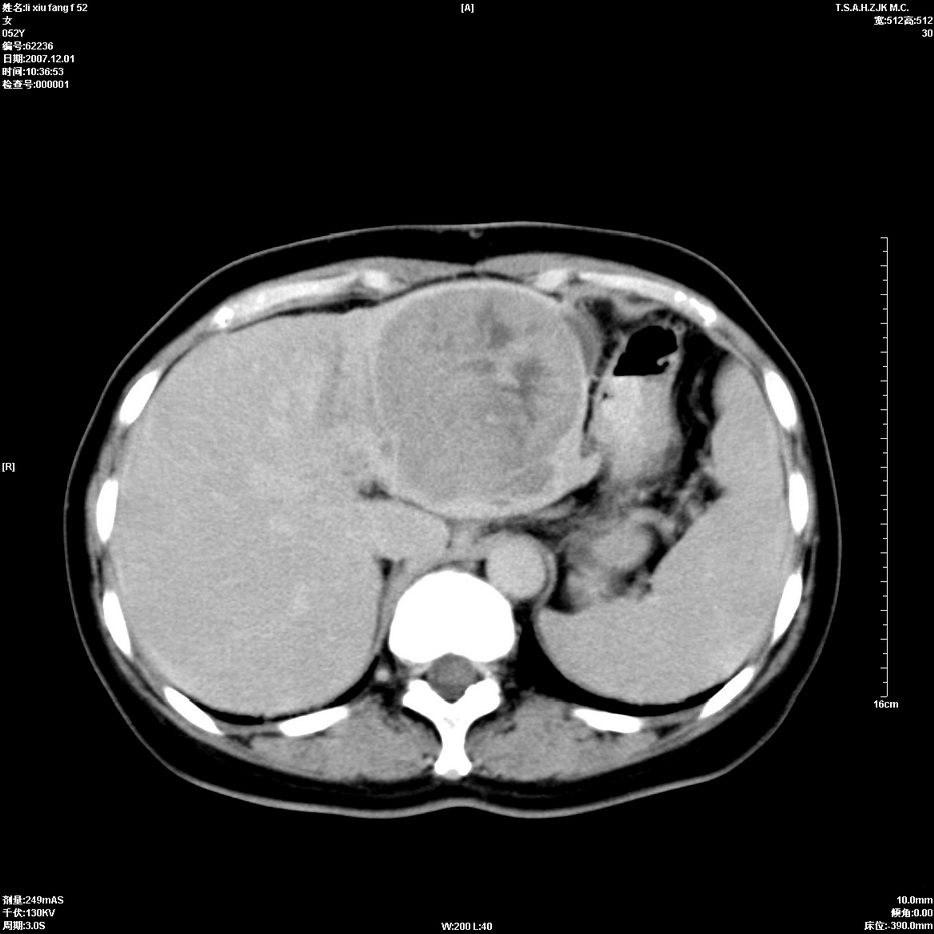

标题: CT12858:女,52岁,胎甲球蛋白861肝左叶占位,肝癌。下腔静 [打印本页]

标题: CT12858:女,52岁,胎甲球蛋白861肝左叶占位,肝癌。下腔静

肝左叶巨大低密度灶肿块,增强符合快进快出表现,有动静脉交通支;静脉期,下腔静脉内有充盈缺损,afp明显升高,支持肝癌并下腔静脉癌栓形成。

支持楼主   门静脉主干及左支癌栓形成

以下是引用拾荒者在2008-4-15 22:57:00的发言:[br]肝左叶巨大低密度灶肿块,增强符合快进快出表现,有动静脉交通支;静脉期,下腔静脉内有充盈缺损,afp明显升高,支持肝癌并下腔静脉癌栓形成。